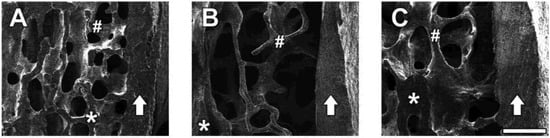

Representative SE photomicrographs of each treatment group are shown in Figure 6. SE images revealed that OVX induced significant bone loss in trabecular bone areas (indicated as #) and reduced bone density (represented as dark grey color compared with the sham group) whereas the sham group showed densely packed spaces in trabecular bone. Administration of CH improved the micro-architecture of bones with thicker trabecular bone, increased bone density, and maintained the intactness and integrity of the trabecular bone, indicating its usefulness in the prevention of bone loss. However, cortical bone (indicated by an arrow) is not significantly affected by OVX (A; sham vs. B; OVX), while administration of 1.0% CH in OVX rats exhibited slightly thicker cortical bone (C), although this was not statistically significant.

Figure 6.

(A) Electron microscopic images of lumbar vertebrae in sham group, (B) OVX group, and (C) CH treated group. Secondary emission images of the lumbar vertebral body (centrum) which was cut sagittally on the half line. Arrow shows the cortical bone of the vertebral body. The asterisk area (*) is the cutting surface of cancellous bone. The trabecular bone areas (#) are placed on the left side of cortical bone (arrow). (A) Sham group showed densely packed space in the trabecular bone. (B) OVX group showed a thin trabecular bone (#) and the bone density was very low. (C) CH treated group showed a thicker trabecular bone compared with OVX and the bone density was higher than OVX. Scale bar = 200 μm.